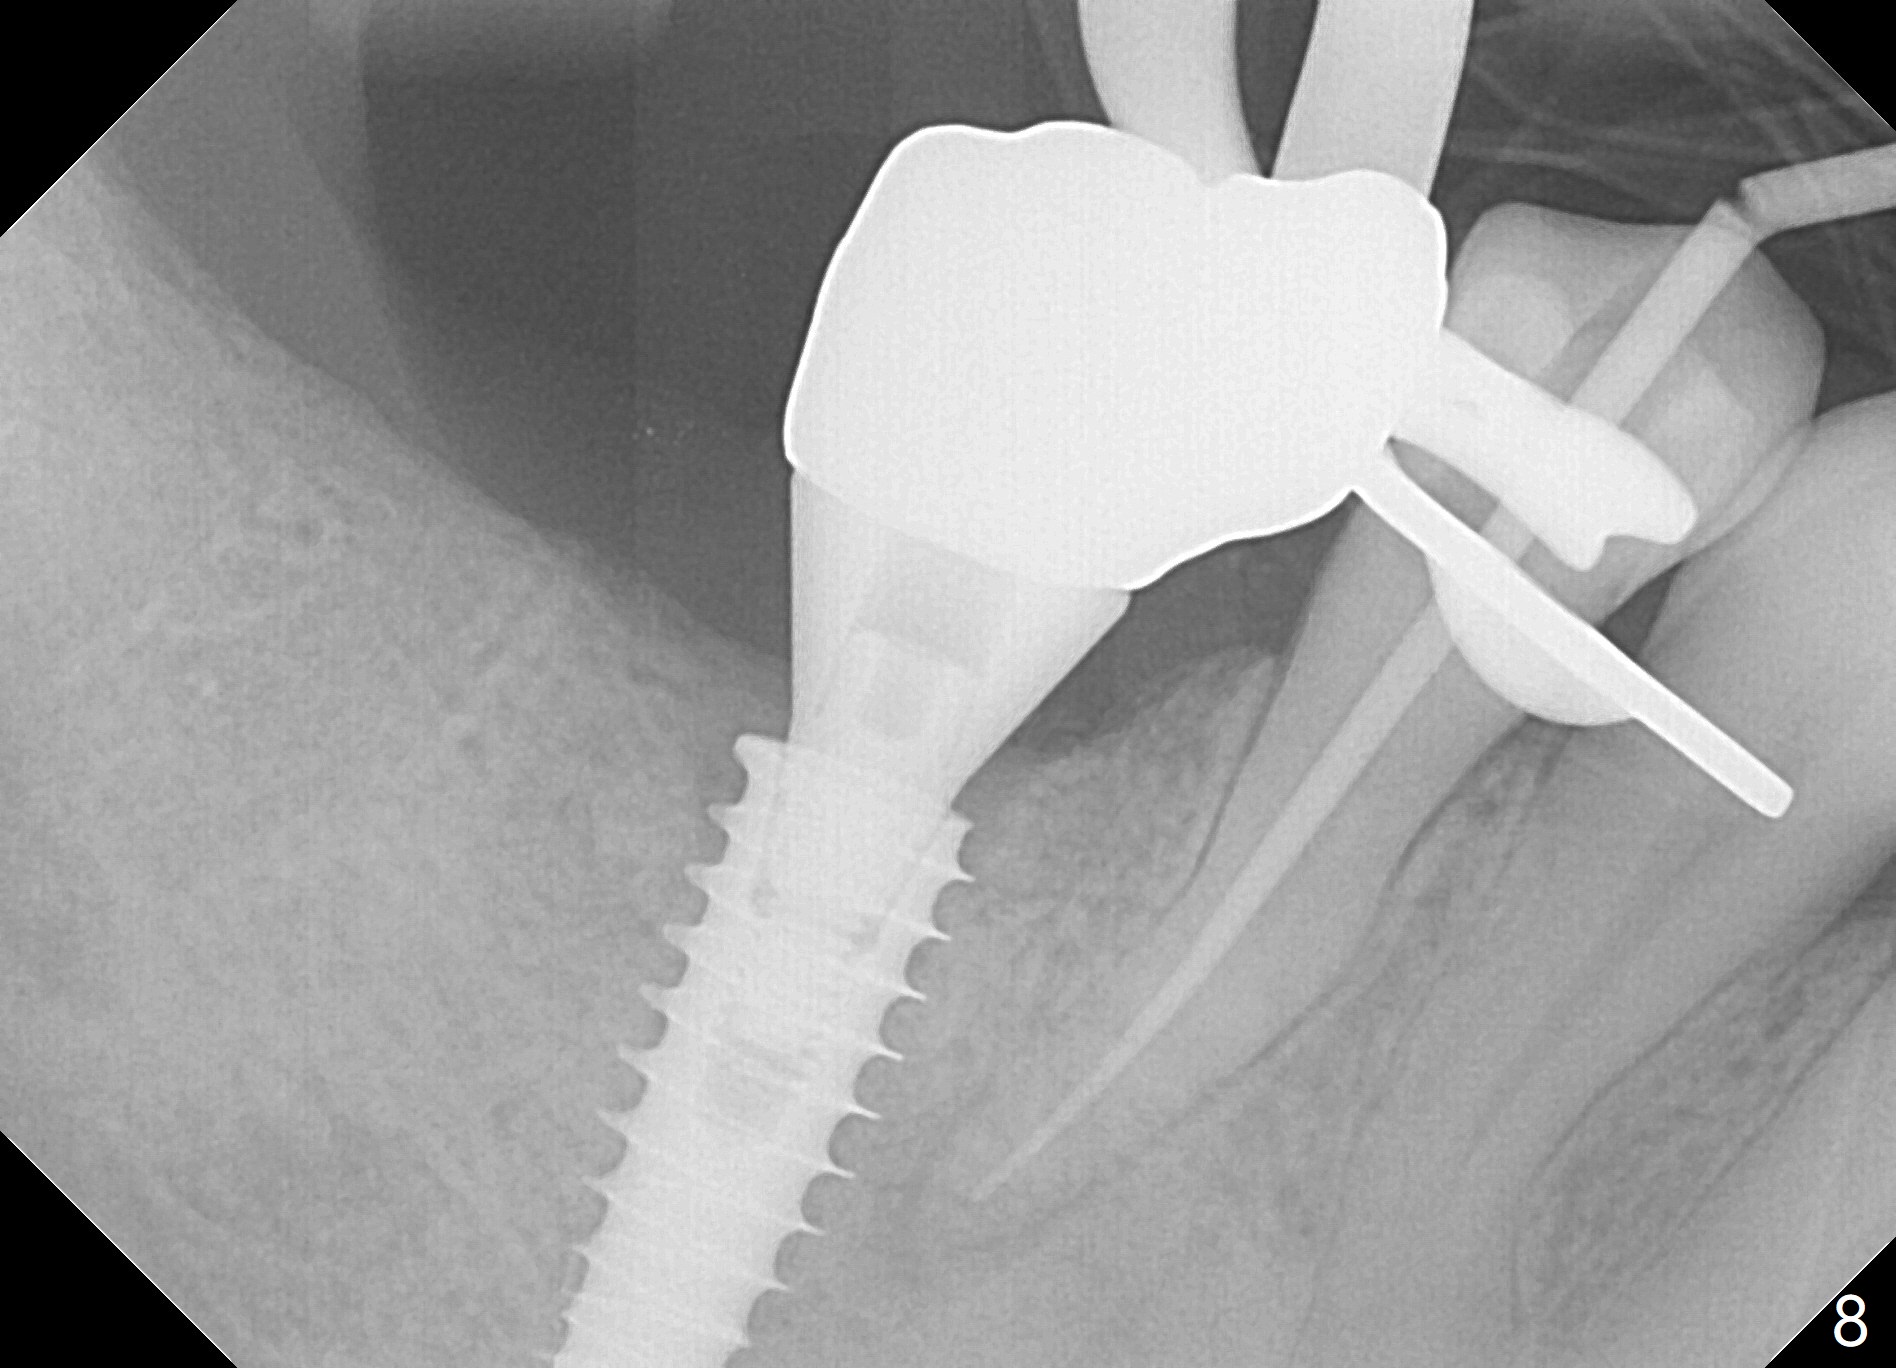

Bone graft seems to sink down and becomes denser 3 months postop (Fig.6 arrow). The bone continues being denser 5 months postop (Fig.7). There is periapical radiolucency of the tooth #29 (^). RCT is done (Fig.8). The pain persists 2 weeks postop (Fig.9,10). There is no missing canal (Fig.9). The apex is close to the implant (Fig.9 *). Apicoectomy will be performed if needed. It appears that the implant is also placed buccal (Fig.10 <) and/or the implant too large for the site. Therefore there should be a 2-3 mm buccal gap before and after implant placement. Separation and reflection of the buccal flap allows better visibility. The pain persists 1 month post RCT and 6 months post implant placement. RCT retreatment is initiated (Fig.11,12) with placement of Calcium Hydroxide paste after redebridement with 30/.04 rotary file at 23.5 mm (.5 mm longer than the earlier RCT, Fig.13). RCT retreatment finishes with apparent transportation and extrusion in 4 weeks (Fig.14,15), followed by apicoetomy (Fig.16,17) (20 days later)). Discomfort remains 2.5 months postop (Fig.18). Keep watching.